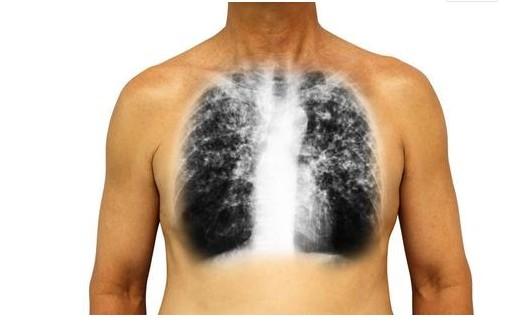

肺癌是惡性腫瘤之一,居男性惡性腫瘤首位。

一提到肺癌,多數人就會想到咳血、消瘦,其實,肺癌還有其他不典型的症狀。

一旦「這裡」開始疼,十有八九是肺癌,三類人最好去檢查一下!